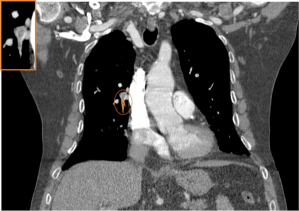

Defecto de repleción parcial periférico con rectificación de la pared de la arteria pulmonar derecha, sugestivo de estigmas de TEP crónico

Defecto de repleción parcial y periférico con ángulo obtuso en arteria lobar inferior derecha (amarillo), sugestivo de TEP crónico. Arteria lobar del LM con aumento de calibre y signo de angulo agudo, sugestivo de TEP agudo. Distal al trombro la arteria segmentaria ha disminuido el calibre por ausencia de flujo (rosa).